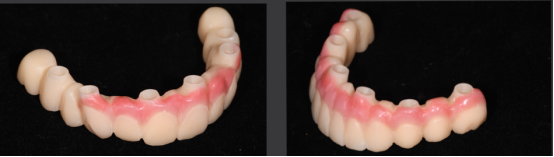

· 最终修复体采用士卓曼原厂切削纯钛桥架+氧化锆整体桥。

· 数字化设计第二幅临时修复体,PMM切削,上下颌各修复12个单位的修复体,16.26单端桥设计

· 第二幅临时修复体戴入口内,修复效果良好,前伸侧方咬合无干扰,预留清洁通道。

· 临时修复体仓扫后回切设计纯钛桥架。

· 制作士卓曼原厂切削纯钛桥架+氧化锆整体桥+龈瓷。

· 修复体红白美学满意,前伸侧方咬合均无干扰,前牙前突问题解决,指导患者清洁。